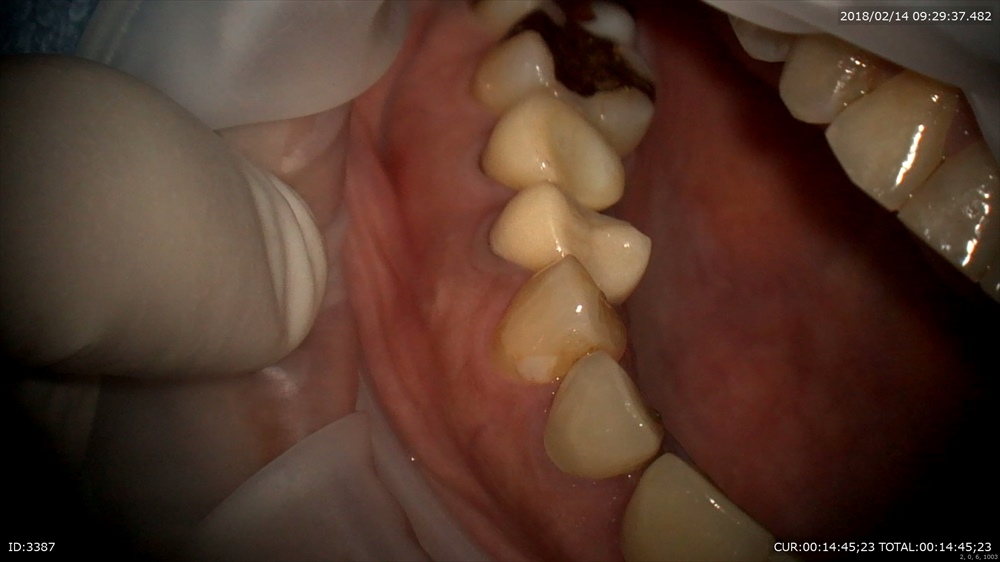

抜歯後、お掃除

装置装着 デーモンシステム。師事している武内先生が第一人者のシステム。本当に矯正期間が短い。弱い力で動くので痛くない。私は色々なシステムをこれまで使用しましたが歯周組織にも優しいのは私の臨床に大切です。

マイクロスコープで正確に。

六番、七番間にミニスクリュー。

次の方は精密根管治療が終了しかぶせ物の型取り。

仮歯を外して

型取り

写真を撮ってどれがかぶせ物かわからないようにオーダーメイドへ。セラミスト間中先生の出番。